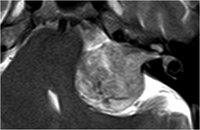

Akustikusneurinom T1 mit KM - axial

Akustikusneurinom mit typischem "Eistüten"-Bild.